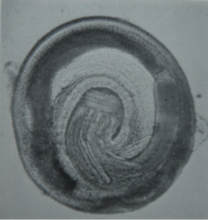

幼蟲

幼蟲發育至第三期盤曲呈“6”字形,長約4mm,頭頂部具唇,頭球上都具4環小鉤,其數目和形狀有重要的蟲種鑑別意義。全身被有200列以上的環列體棘,體前部的棘長10mm,往後逐漸變小,變稀。在體前1/4體內有4個肌質的管狀頸囊,各自開口於頭球內的氣室中,內含漿液,這四個構造對頭球的膨脹和收縮有重要作用。食管棒狀,分為肌性和腺性兩部分。